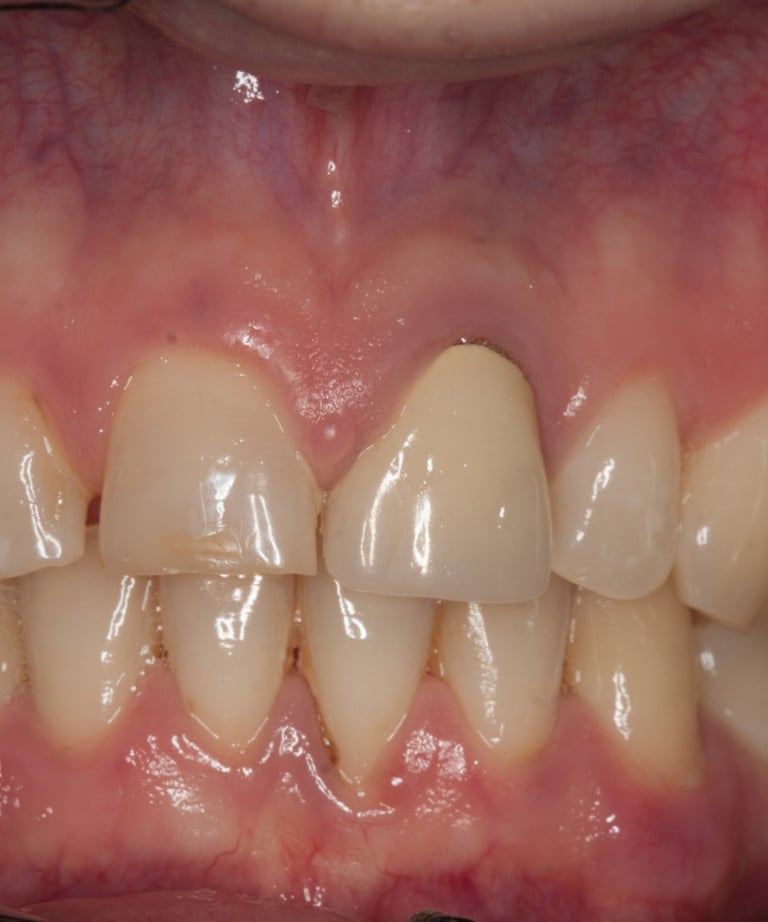

Il paziente si è presentato con una corona decementata ripetutamente sul dente 21, con un'evidente discrepanza estetica rispetto ai denti naturali adiacenti. L’elemento non si armonizzava con i tessuti circostanti e presentava problemi sia funzionali che estetici. Dopo una valutazione clinica approfondita, sono emersi i seguenti problemi:

Corona incongrua: Esteticamente non soddisfacente e incapace di mimetizzarsi con i denti naturali vicini.

Prima:

Corona visibilmente discromica rispetto ai denti naturali.

Decementazione frequente della corona.

Perno moncone non funzionale e trattamento endodontico insufficiente.